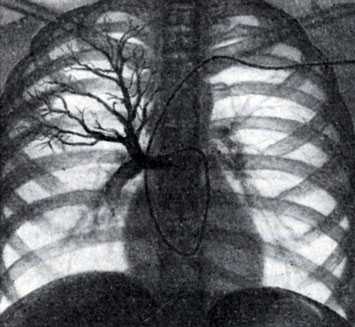

Применяют две методики ангиопульмонографии: общую и селективную; разновидностью селективной ангиопульмонографии является концевая ангиопульмонография.

Рис. 2. Селективная ангиопульмонография. Катетер (виден под ключицей, вдоль позвоночника и в области сердца) введен в верхнезональную артерию правого легкого. Видны контрастированные сосуды верхней зоны

Для осуществления общей ангиопульмонографии контрастное вещество в количестве 50—70 мл вводят внутривенно (обычно через локтевую вену) или в полость правого сердца (см. Ангиокардиография) при помощи введенного через вену катетера (рис. 1). При селективной ангиопульмонографии (рис. 2) контрастное вещество вводят в одну из ветвей легочного ствола; для этой цели катетер проводят через правое сердце в легочный ствол и далее в легочную артерию. Для контрастирования одного легкого применяют 20—30 мл контрастного вещества, для исследования одной зоны — 10—15 мл.

Рис. 3. Концевая ангиопульмонография. Катетер (виден под ключицей, вдоль позвоночника и в области сердца) введен в верхнесегментарную артерию верхней зоны правого легкого. Видны концевые артериальные разветвления. Контрастированы пути венозного оттока данного сегмента

Селективная ангиопульмонография позволяет одновременно измерять давление в полостях сердца и легочного ствола и определять степень насыщения крови кислородом. При концевой пнгиопульмонографии катетер вводят в одну из сегментарных ветвей легочной артерии (рис. 3),после чего инъецируют 5—8 мл контрастного вещества. Кроме описанных методик, ангиопульмонография может быть выполнена путем чрескожной пункции бедренной или подключичной вены по способу Сельдингера (с последующим введением зонда).

Различают три фазы контрастирования сосудов легких: артериальную, продолжающуюся 3—5 секунд, капиллярную, или паренхиматозную, продолжительностью в 1-3 секунды, и венозную, длящуюся 4—7 секунд. Для изучения легочного кровообращения проводят серию снимков на сериографе по следующей примерной программе: 2 снимка в 1 секунду в течение 3 секунд, затем 1 снимок в 1 секунду в течение 10 секунд.

Ангиопульмонография - метод рентгенологической диагностики состояния лёгочного кровообращения путём введения рентгеноконтрастных веществ в артерии лёгких. Выделяют общую и селективную ангиопульмонографию. При общей ангиопульмонографии контрастное вещество вводят в ствол лёгочной артерии, при этом заполняются все сосуды малого круга кровообращения. При селективной контраст вводится лишь в одну из ветвей лёгочной артерии и оценивается состояние кровотока только одного лёгкого или его доли.

- При оценке результатов исследования обнаруживают патологические изгибы сосудов лёгких, участки их сужения, расширения, наличие дополнительных ветвей.

- При тромбоэмболии легочной артерии на снимке точно виден тромб, можно определить его размеры и локализацию.

- По характеру сосудистого рисунка можно судить о наличии опухоли в лёгком.

Таким образом, ангиопульмонография является золотым стандартом в диагностике тромбоэмболии легочной артерии, так как не только подтверждает наличие либо отсутствие тромба, но и определяет локализацию и размеры.